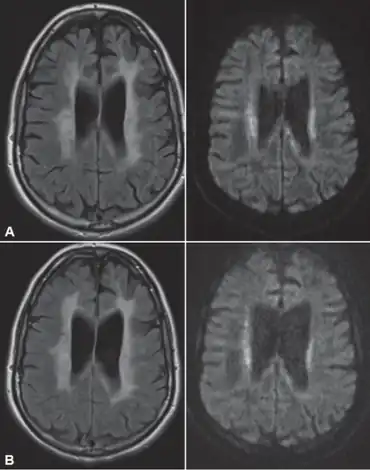

Neuroimaging

Standard MRI scans have been performed on 1.5 Tesla scanners with 5 mm thickness and 5 mm spacing to screen for white matter lesions in identified families. If signal intensities of the MRI scans are higher in white matter regions than in grey matter regions, the patient is considered to be at risk for HDLS, although a number of other disorders can also produce white matter changes and the findings are not diagnostic without genetic testing or pathologic confirmation.[2]